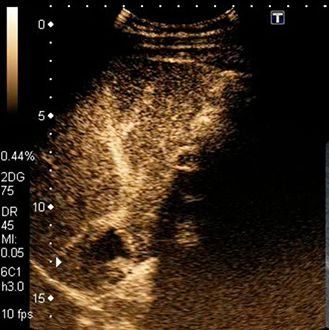

Dentro del ámbito del diagnóstico médico, la ecografía desempeña un papel crucial al proporcionar una visión detallada del interior del cuerpo.

Utilizando ondas de ultrasonido, esta técnica no invasiva permite obtener imágenes en tiempo real de órganos y tejidos internos. Los profesionales de la salud utilizan estas imágenes para evaluar la salud y detectar posibles problemas en diversas áreas del cuerpo. En esta sección, examinaremos en profundidad cómo el radiodiagnóstico con ecografía se ha convertido en una herramienta indispensable en el campo de la medicina moderna, brindando información valiosa para el diagnóstico y tratamiento de una amplia gama de condiciones médicas.